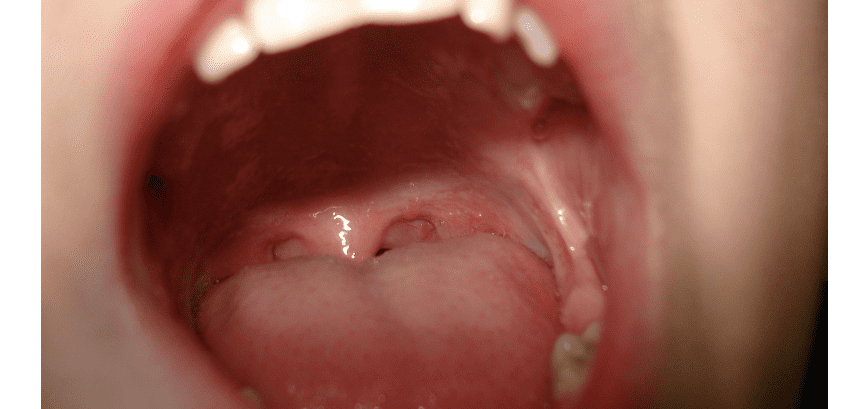

혓바늘이 돋는 이유에 대해 알아보려고 합니다. 혓바늘은 많은 사람들이 경험하는 불편한 증상 중 하나로, 다양한 원인에 의해 발생할 수 있습니다. 피부 염증이나 습진, 자극적인 음식물 섭취, 알레르기 반응, 스트레스와 불안 등이 혓바늘이 생길 수 있는 주요 원인입니다.

이러한 원인들을 이해하고 예방하는 방법을 알면 혓바늘을 효과적으로 관리할 수 있습니다. 다음으로, 각각의 원인에 대해 자세히 알아보도록 하겠습니다. 함께 알아보면서 건강한 구강과 편안한 일상을 찾아가 보시길 바라겠습니다.